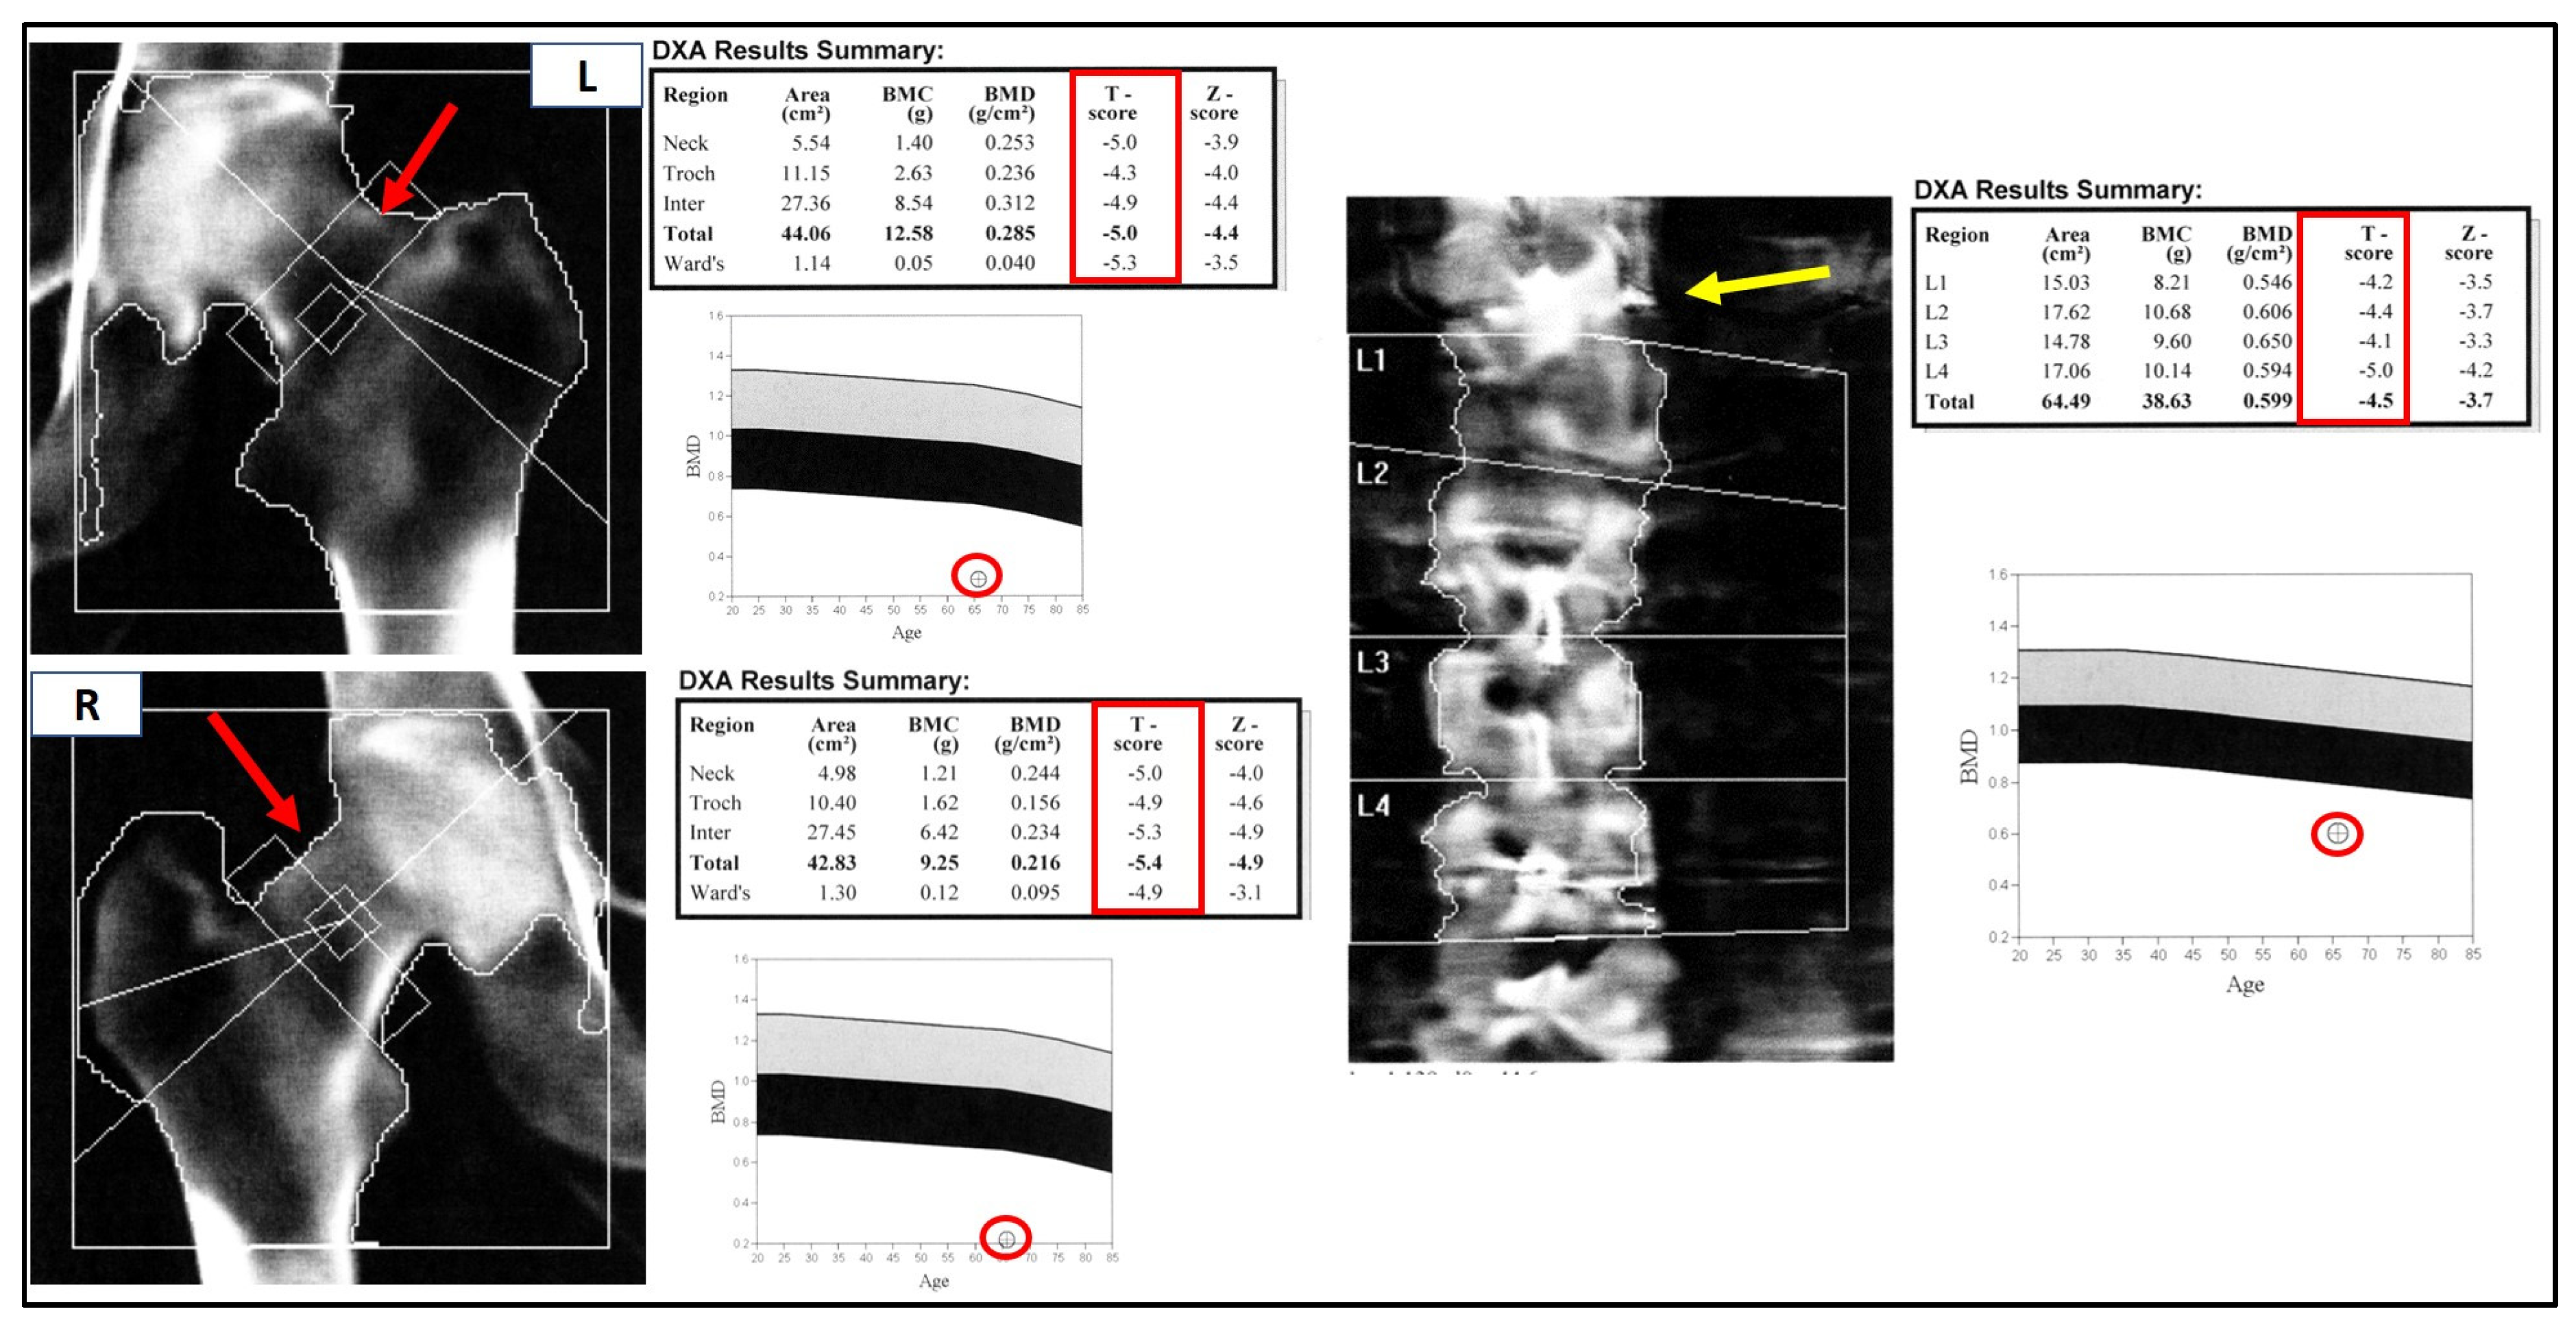

Bone mass evaluation by dual energy X-ray absorptiometry (DEXA), reported in Figure 3, showed severe osteoporosis of both femurs (T-score −5.0 and −5.4 SD for left and right, respectively) and the lumbar spine (T-score −4.5 SD).

Although the DEXA cannot be considered a radiological examination/imaging diagnostic tool, the left femoral neck appeared much shorter, compatible with a closed fracture. Moreover, and more interestingly, at the T12/L1 spine level, an hyperdense area was clearly detectable. This was further investigated by the mean of Global PET Ga68, that showed hypercaptation at the expansive formation in T12-L1 with narrowing of the vertebral canal and bone lysis at the L1 vertebral body and transverse and spinous processes levels. Moreover, the exam denoted an increased uptake in a small encephalic area of the frontal cortex (Figure 4A,B).

Figure 3. Bone mass evaluation by DEXA. The hips are shown at the right of the figure (left hip, L, above; right hip, R, below), the spine is on the left. The bone densitometry values (shown in the DXA results summary table) are far below the osteoporotic threshold (T-score < −2.5 SD). The inferior panels report the patient’s bone mineral density (BMD) levels compared to those expected at the same site for age-matched subjects: normal values above the grey band (osteopenic) and frankly osteoporotic below the black band (osteoporotic). The different length of the right and left femoral necks, indicated by the red arrows, may indicate a closed fracture. The hyperdense area at T12-L1 is indicated by a yellow arrow.